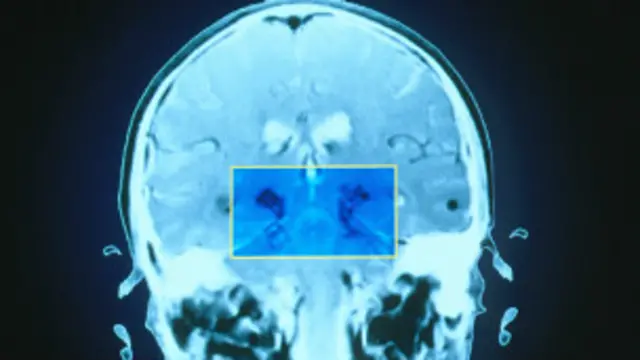

El Parkinson se produce como consecuencia de la destrucción de neuronas productoras de dopamina, fundamentales en el control de los movimientos del cuerpo.